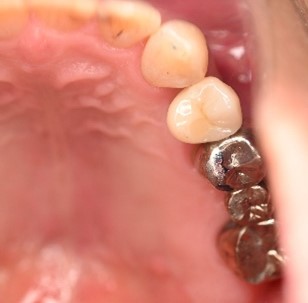

After